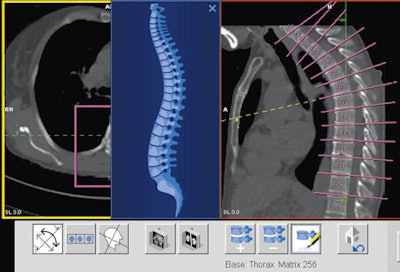

In this case of lymphoma, the VRT image shows multiple enlarged lymph nodes in the mediastinum and anatomical details in the lungs. Image courtesy of Clinique Sainte Marie, Paris.